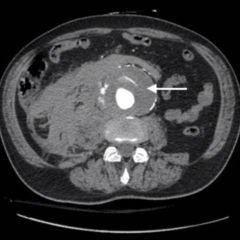

Although mesenteric ischemia accounts for only 1% of emergency department visits, it carries a high mortality rate.1-3. The overall mortality associated with mesenteric ischemia is between 60% to 90% and climbs exponentially once bowel wall infarction occurs.2,3 Acute arterial occlusion is the most familiar form of mesenteric ischemia. However, there are other forms of mesenteric ischemia that are not as well recognized or well known that still carry significant mortality rates. Early recognition, diagnosis and treatment are the mainstays in reducing the mortality of this condition.1Knowing all forms of mesenteric ischemia is essential for an emergency medicine clinician.